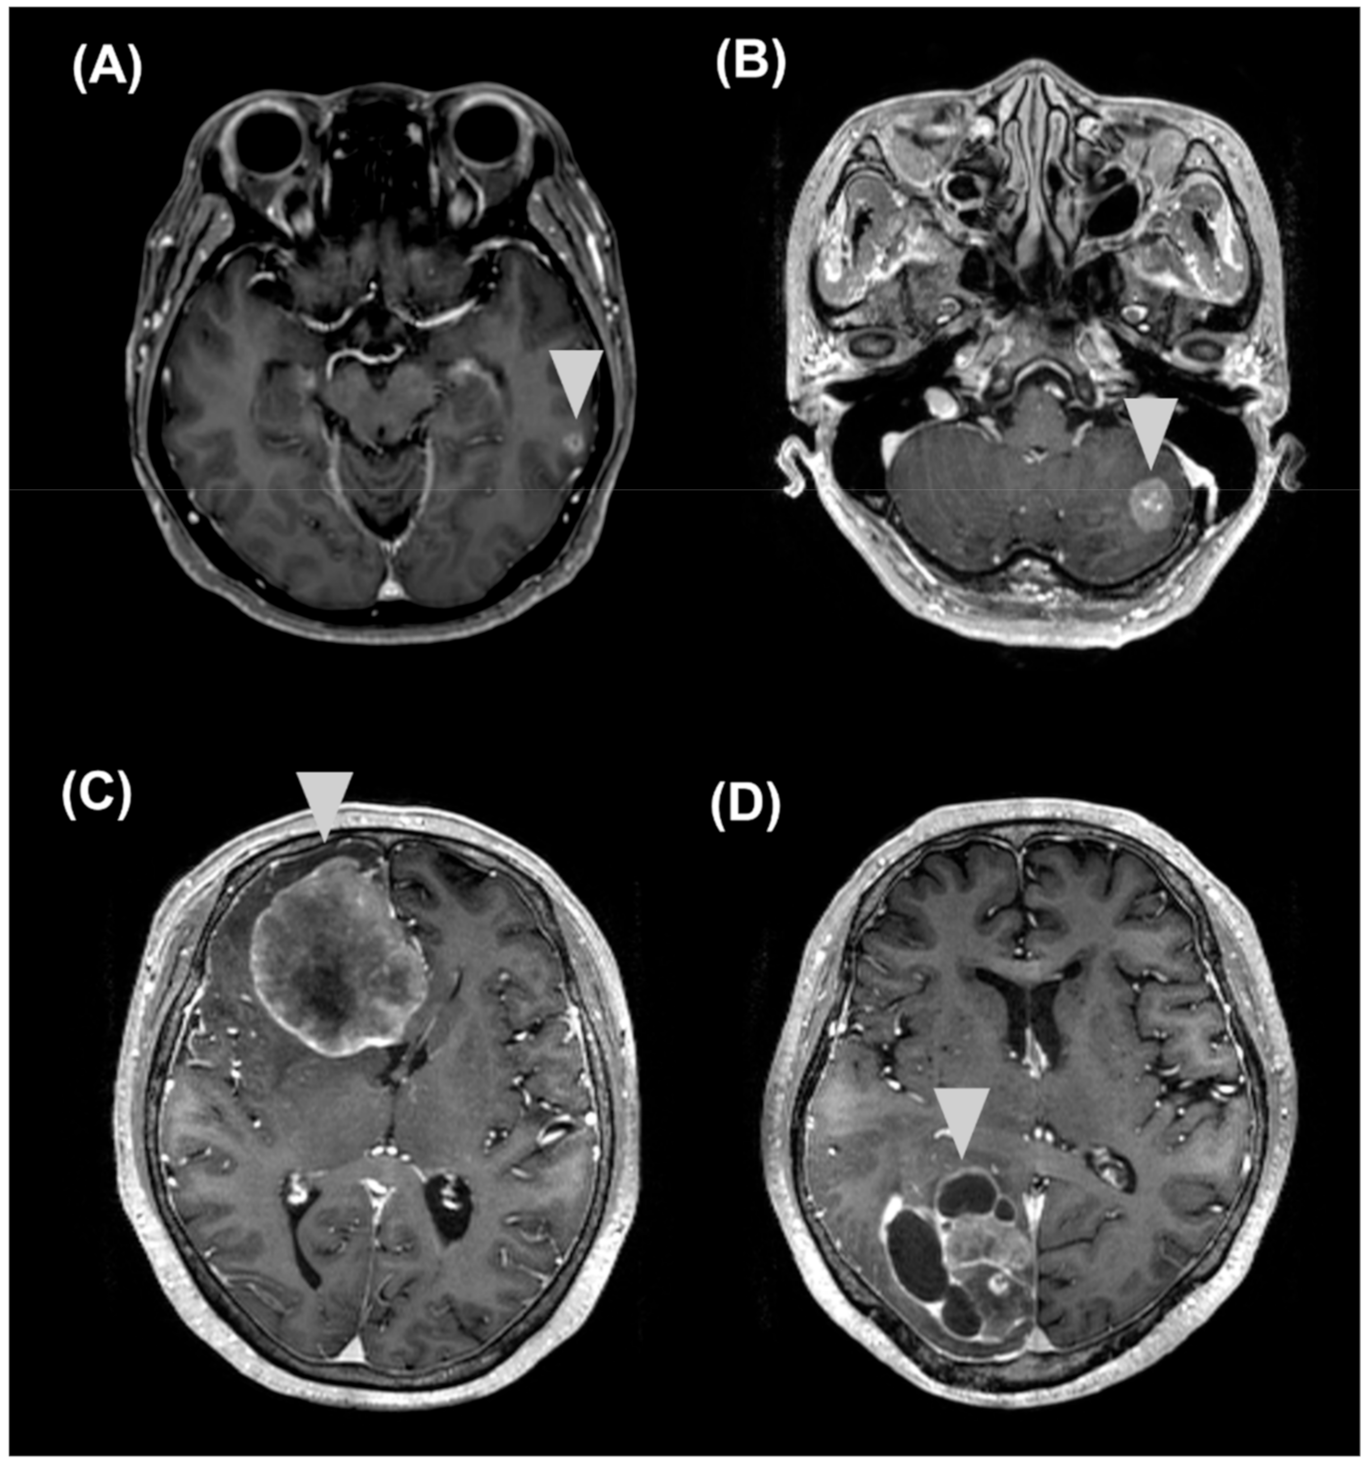

2.4. Correlations of sNFL and sGFAP Levels with Clinical and MRI Features

2.5. Longitudinal Follow-Up